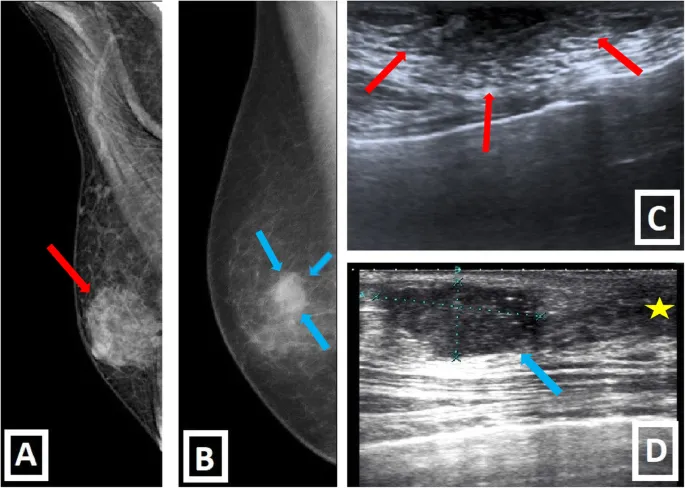

🩺 Diagnosis - Spotting the Suspect

Initial Evaluation: Any palpable, firm, subareolar mass in a male is the most common presentation.

- Assess for nipple retraction, bloody discharge, skin changes (dimpling, ulceration), or axillary lymphadenopathy.

Diagnostic Pathway:

- Biopsy:

- Core Needle Biopsy (CNB) is the gold standard. It provides tissue for histology and receptor testing (ER, PR, HER2).

- Fine-Needle Aspiration (FNA) is less preferred due to high inadequacy rates.

⭐ Pearl: Unlike in females, screening mammography is not recommended for asymptomatic men. Diagnosis is prompted by symptoms.